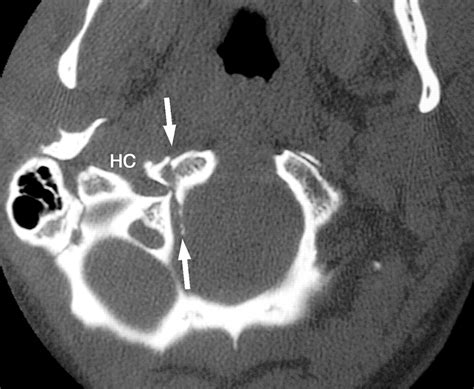

• Computed Tomography (CT) Scan: This is the gold standard for diagnosing occipital condyle fractures. CT scans provide detailed images of the bony structures and can help identify the location and extent of the fracture.

Occipital condyle fractures are classified based on their pattern and mechanism of injury. The most commonly used classification system is the Anderson and Montesano classification, which categorizes these fractures into three types:

Type Description Mechanism of Injury

Type I Compression fracture of the occipital condyle Axial loading with compression

Type II Basilar skull fracture extending into the occipital condyle Lateral mass displacement

Type III Avulsion fracture of the occipital condyle Altered rotational forces